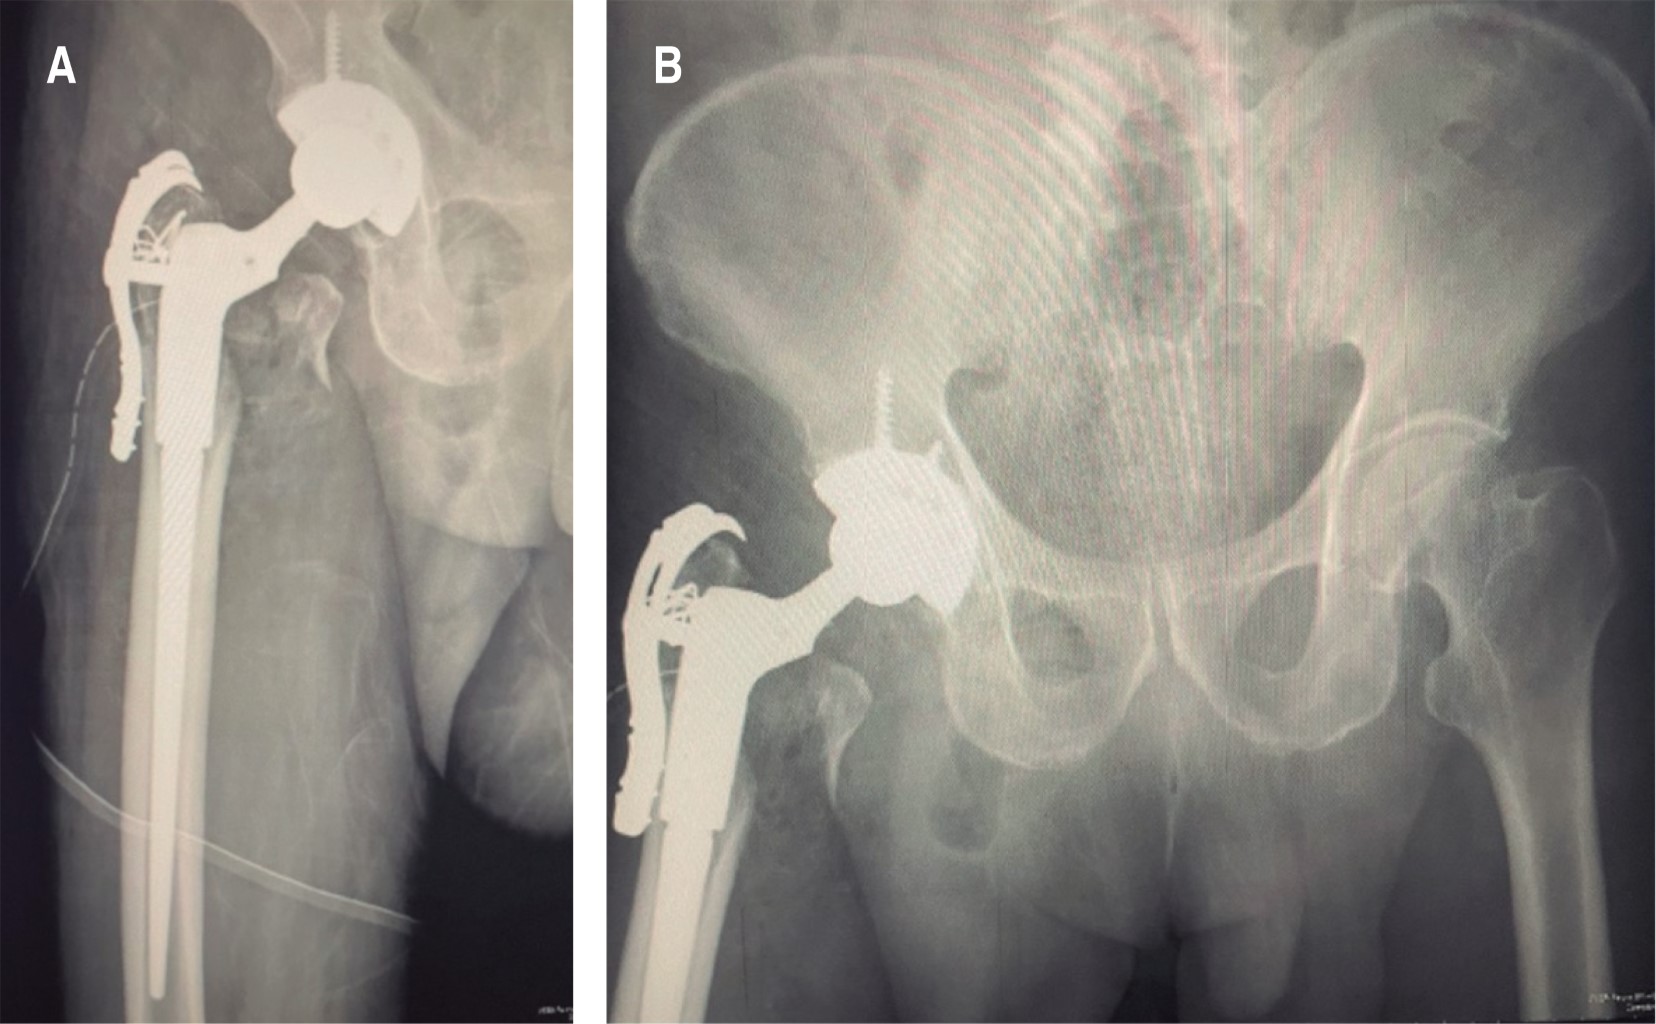

Técnica quirúrgica: Se realiza el procedimiento a las tres semanas de hospitalizado, por cuestiones de disponibilidad de material. Se posiciona en decúbito lateral izquierdo, abordaje posterolateral, sin necesidad de realizar miotomía de glúteo medio, ya que se encontraba conminuta su inserción, por lo que se refirió el músculo junto con trocánter hacia anterior, exponiendo así la base del cuello, el cual se extrae completamente con cabeza femoral al realizar la capsulotomía. Se realiza rimado progresivo hasta 52, y se coloca copa acetabular primaria 53 mm, obteniéndose adecuado press-fit, inserto regular para cabeza 32. Se procedió a trabajar fémur con rima iniciadora y rimado para componente distal de vástago femoral de longitud 110 mm hasta 13 mm de diámetro (Figura 2A), se coloca cuello modular Bx 55 mm y cabeza 32 neutra de prueba; se realizan pruebas de forma correcta sin luxar, por lo que se colocan componentes definitivos y se procede al armado del mecanismo abductor, se coloca garra larga y se fija en cuello del componente femoral (Figura 2B); se corrobora la posición de componentes con fluoroscopia y se procede a cerrar por planos; se agregan puntos de reforzamiento con PDS del glúteo hacia la garra trocantérica. Se reporta un sangrado de 550 cm3 y duración de 3.5 horas de procedimiento quirúrgico, el cual finaliza sin eventualidades, no se coloca drenaje.

Figura 2

Figura 3